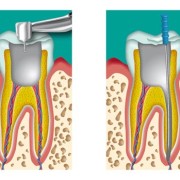

Sorriso e Salute si occupa di estetica del sorriso, radiologia endorale, prevenzione dentale, riabilitazione protesica, chirurgia orale, ortodonzia fissa e mobile ed invisibile tramite mascherine, impianti-endossei e pedodonzia.

Sorriso e Salute offre una serie di prestazioni a carattere innovativo ed alto contenuto tecnologico nel campo odontoiatrico, tra cui tecniche indolore per l’attività conservativa, tecniche indolore di courettage con utilizzo di ultrasuoni. Le attrezzature e gli impianti di cui disponiamo sono rigorosamente a norma e tra i più innovativi.